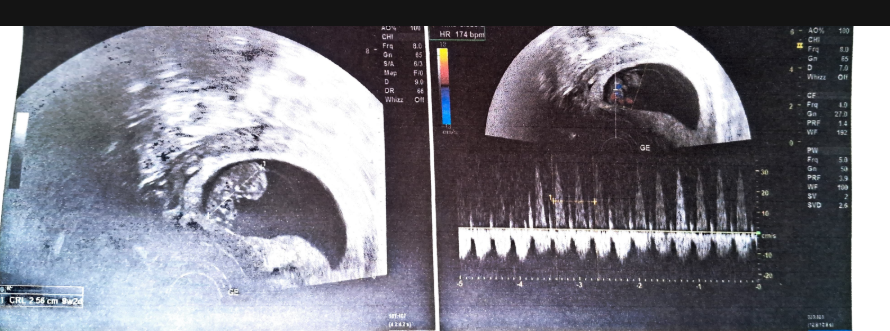

Right from the beginning, I was clearly guided on all the medical aspects. I knew when each scan had to be taken, what it was for, and what to expect in every stage. Instead of feeling anxious before every appointment, I felt prepared and reassured.

During the term scan, Subhashree was told that her baby was measuring slightly on the larger side for her frame. She was immediately scared that this meant a caesarean section was coming, and that everything we had built up toward a normal delivery was now out of reach.

Shobana, our antenatal coach, was at that time travelling in the United States for a relative’s wedding. She did not hesitate. She took out an urgent time slot from her trip to give Subhashree a detailed one-on-one yoga session focused on poses that help the pelvis open and the baby settle into a favourable position for labour. Subhashree followed the routine consistently, which also helped her pelvic floor muscles cooperate during the actual delivery. The result was a smooth, normal delivery.

If my baby is measuring “slightly larger” at the term scan, do I still have a chance at a normal delivery?

Often, yes. A baby measuring slightly on the larger side (but not truly macrosomic) does not automatically mean a caesarean section. What matters alongside baby size is maternal pelvic anatomy, baby’s position, and how well the pelvic floor and surrounding muscles can cooperate during labour. Targeted antenatal yoga, especially poses that help the pelvis open and the baby settle into an optimal position, can make a real difference in the final weeks. Subhashree was told her baby was measuring larger, and she still had a smooth normal delivery of a 3.3 kg baby with pelvic-opening yoga in the lead-up. Our guide on tips for a normal delivery goes deeper into this.